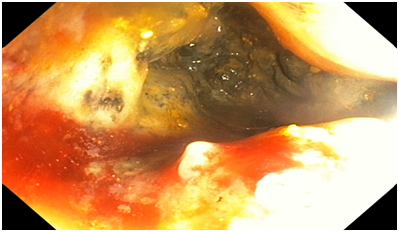

Colonoscopy. The colonoscope was passed all the way down to the ascending colon (distal part). The ascending colon contained circumferential fungating necrotic mass lesion extending all the way down to the caecum. The mass was friable, bled easily both spontaneously and with contact. Multiple biopsy samples were taken from the mass. There was some degree of luminal narrowing as well. The rest of the examined colon all appeared normal. No diverticulum or polyp seen. No observable synchronous tumour seen. Endoscopic Diagnosis was Right-sided colonic adenocarcinoma.

Figure 1 An Endoscopic image of the Hepatic flexure showing the tumour mass.